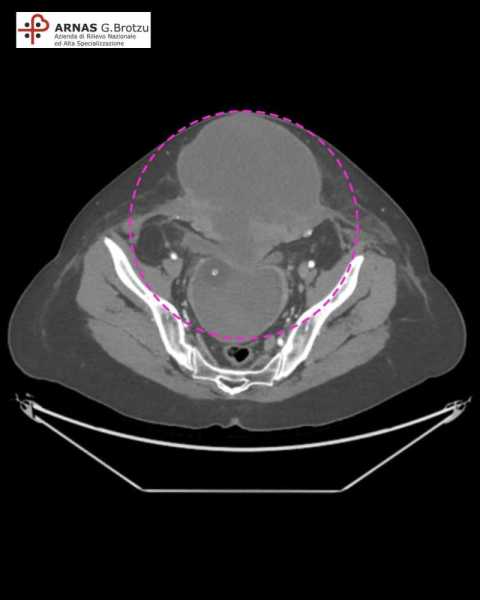

CAGLIARI. Una recidiva di sarcoma dell’utero di oltre tre chili all’addome asportato con successo in una donna di 56 anni. L'intervento, di alta complessità, è stato effettuato il 10 Febbraio al Brotzu di Cagliari dai medici della Struttura di Ginecologia Oncologica, centro di riferimento regionale per la chirurgia oncologica, diretta da Antonio Macciò. La massa asportata, della grandezza di 30 cm per 20 cm, occupava completamente l’addome della donna.

La voluminosa formazione si estendeva dalla cute alla fascia posteriore dei muscoli retti dell’addome, infiltrandoli completamente. Un’estesa incisione ha consentito di individuare all’interno della cavità addominale la massa invasiva, che è stata asportata con cautela ed estrema difficoltà tecnica, che ha necessitato una eviscerazione pelvica totale (asportazione di vescica, retto-sigma) e exeresi dell’intera vagina, completamente occupata da una voluminosa quantità di materiale neoplastico.